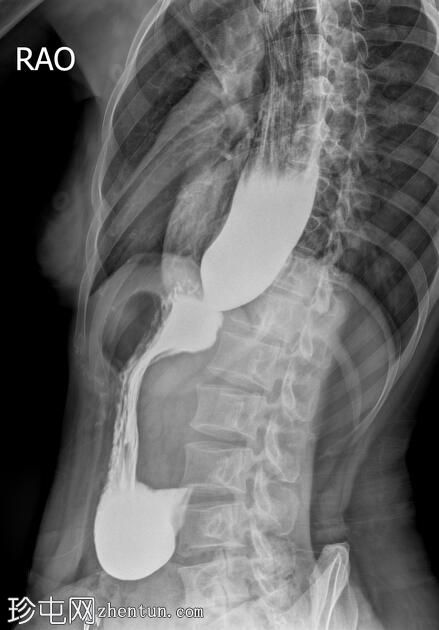

斜位

食管扩张,远端平滑狭窄并呈锥形(鸟嘴状),符合贲门失弛症的特征性表现

食管黏膜形态正常,无异常或溃疡

未见食管裂孔疝

钡餐检查显示食管扩张,远端狭窄并呈锥形,形成符合贲门失弛症特征的鸟嘴状外观。